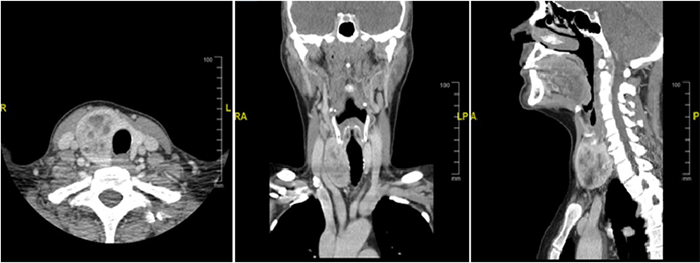

Given this new finding, we completed her MTC workup for tumor markers as well as screening for pheochromocytoma and primary hyperparathyroidism. Her serum level of carcinoembryonic antigen (CEA) and calcitonin were elevated at 16.5 and 392, respectively. She had normal plasma metanephrines, calcium, and parathyroid hormone (PTH). Staging computed tomography (CT) of her neck, chest, abdomen, and pelvis showed no evidence of metastatic disease (Figure 3).

Figure 3. Computed tomography of the neck revealing a large thyroid nodule without evidence of local metastatic disease